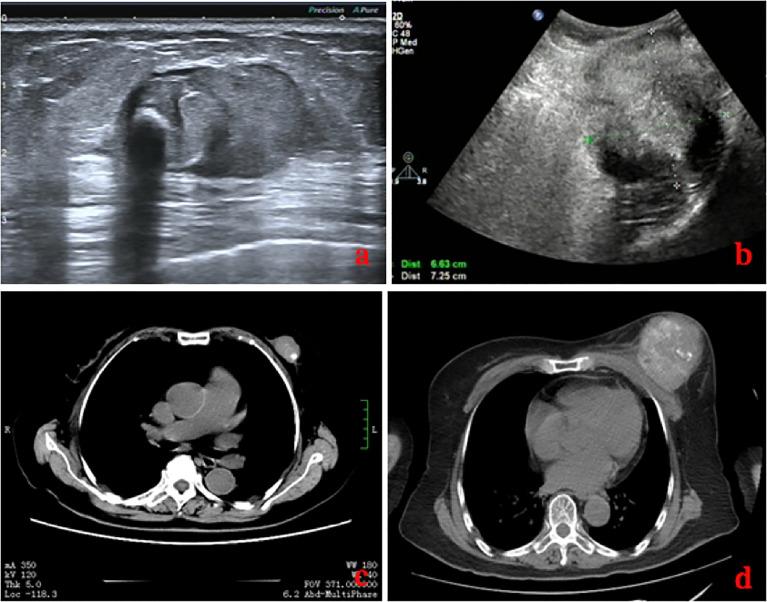

An 83-year-old Chinese woman went to our hospital because of a palpable mass she had had for 8 months in the left breast accompanied by persistent dull pain for 10 days. This mass was initially misdiagnosed as a degenerating fibroadenoma and was graded as probably benign (BI-RADS category 3) by ultrasonography (US) and computed tomography (CT) plain scan and contrast enhancement of chest. Eight months later, it was presumed to be highly malignant and graded as BI-RADS category 4C because of its rapid growth and more calcifications by US and CT. 99mTc-MDP whole-body bone imaging showed that there was a mass-like abnormal radioactive concentration of Tc-99m outside the bone of the left chest. The lumpectomy of the left breast was indicated, and the pathological findings were POB. She succumbed to respiratory failure caused by multiple lung metastases 4 months after the operation.

一名83岁中国女性因左乳可触及肿块8个月且伴有持续钝痛10天前来我院就诊。该肿块最初被误诊为退变的纤维腺瘤,经超声(US)、胸部计算机断层扫描(CT)平扫及增强扫描后被分级为可能良性(BI-RADS 3类)。8个月后,因其生长迅速且经超声和CT显示有更多钙化,被推测为高度恶性,分级为BI-RADS 4C类。99mTc-MDP全身骨显像显示左胸壁外有一肿块样异常放射性锝-99m浓聚。遂行左乳肿块切除术,病理结果为POB。术后4个月,患者因多发肺转移导致呼吸衰竭死亡。